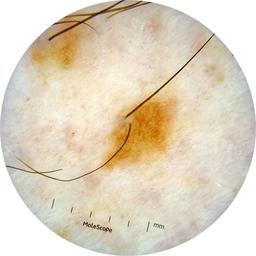

MEL-SELF - Dermoscopic

- Name: MEL-SELF - Dermoscopic

Description:

Dermoscopic lesion images (close-up views of benign and malignant lesions) from the MEL-SELF trial (the Melanoma Self Surveillance trial).